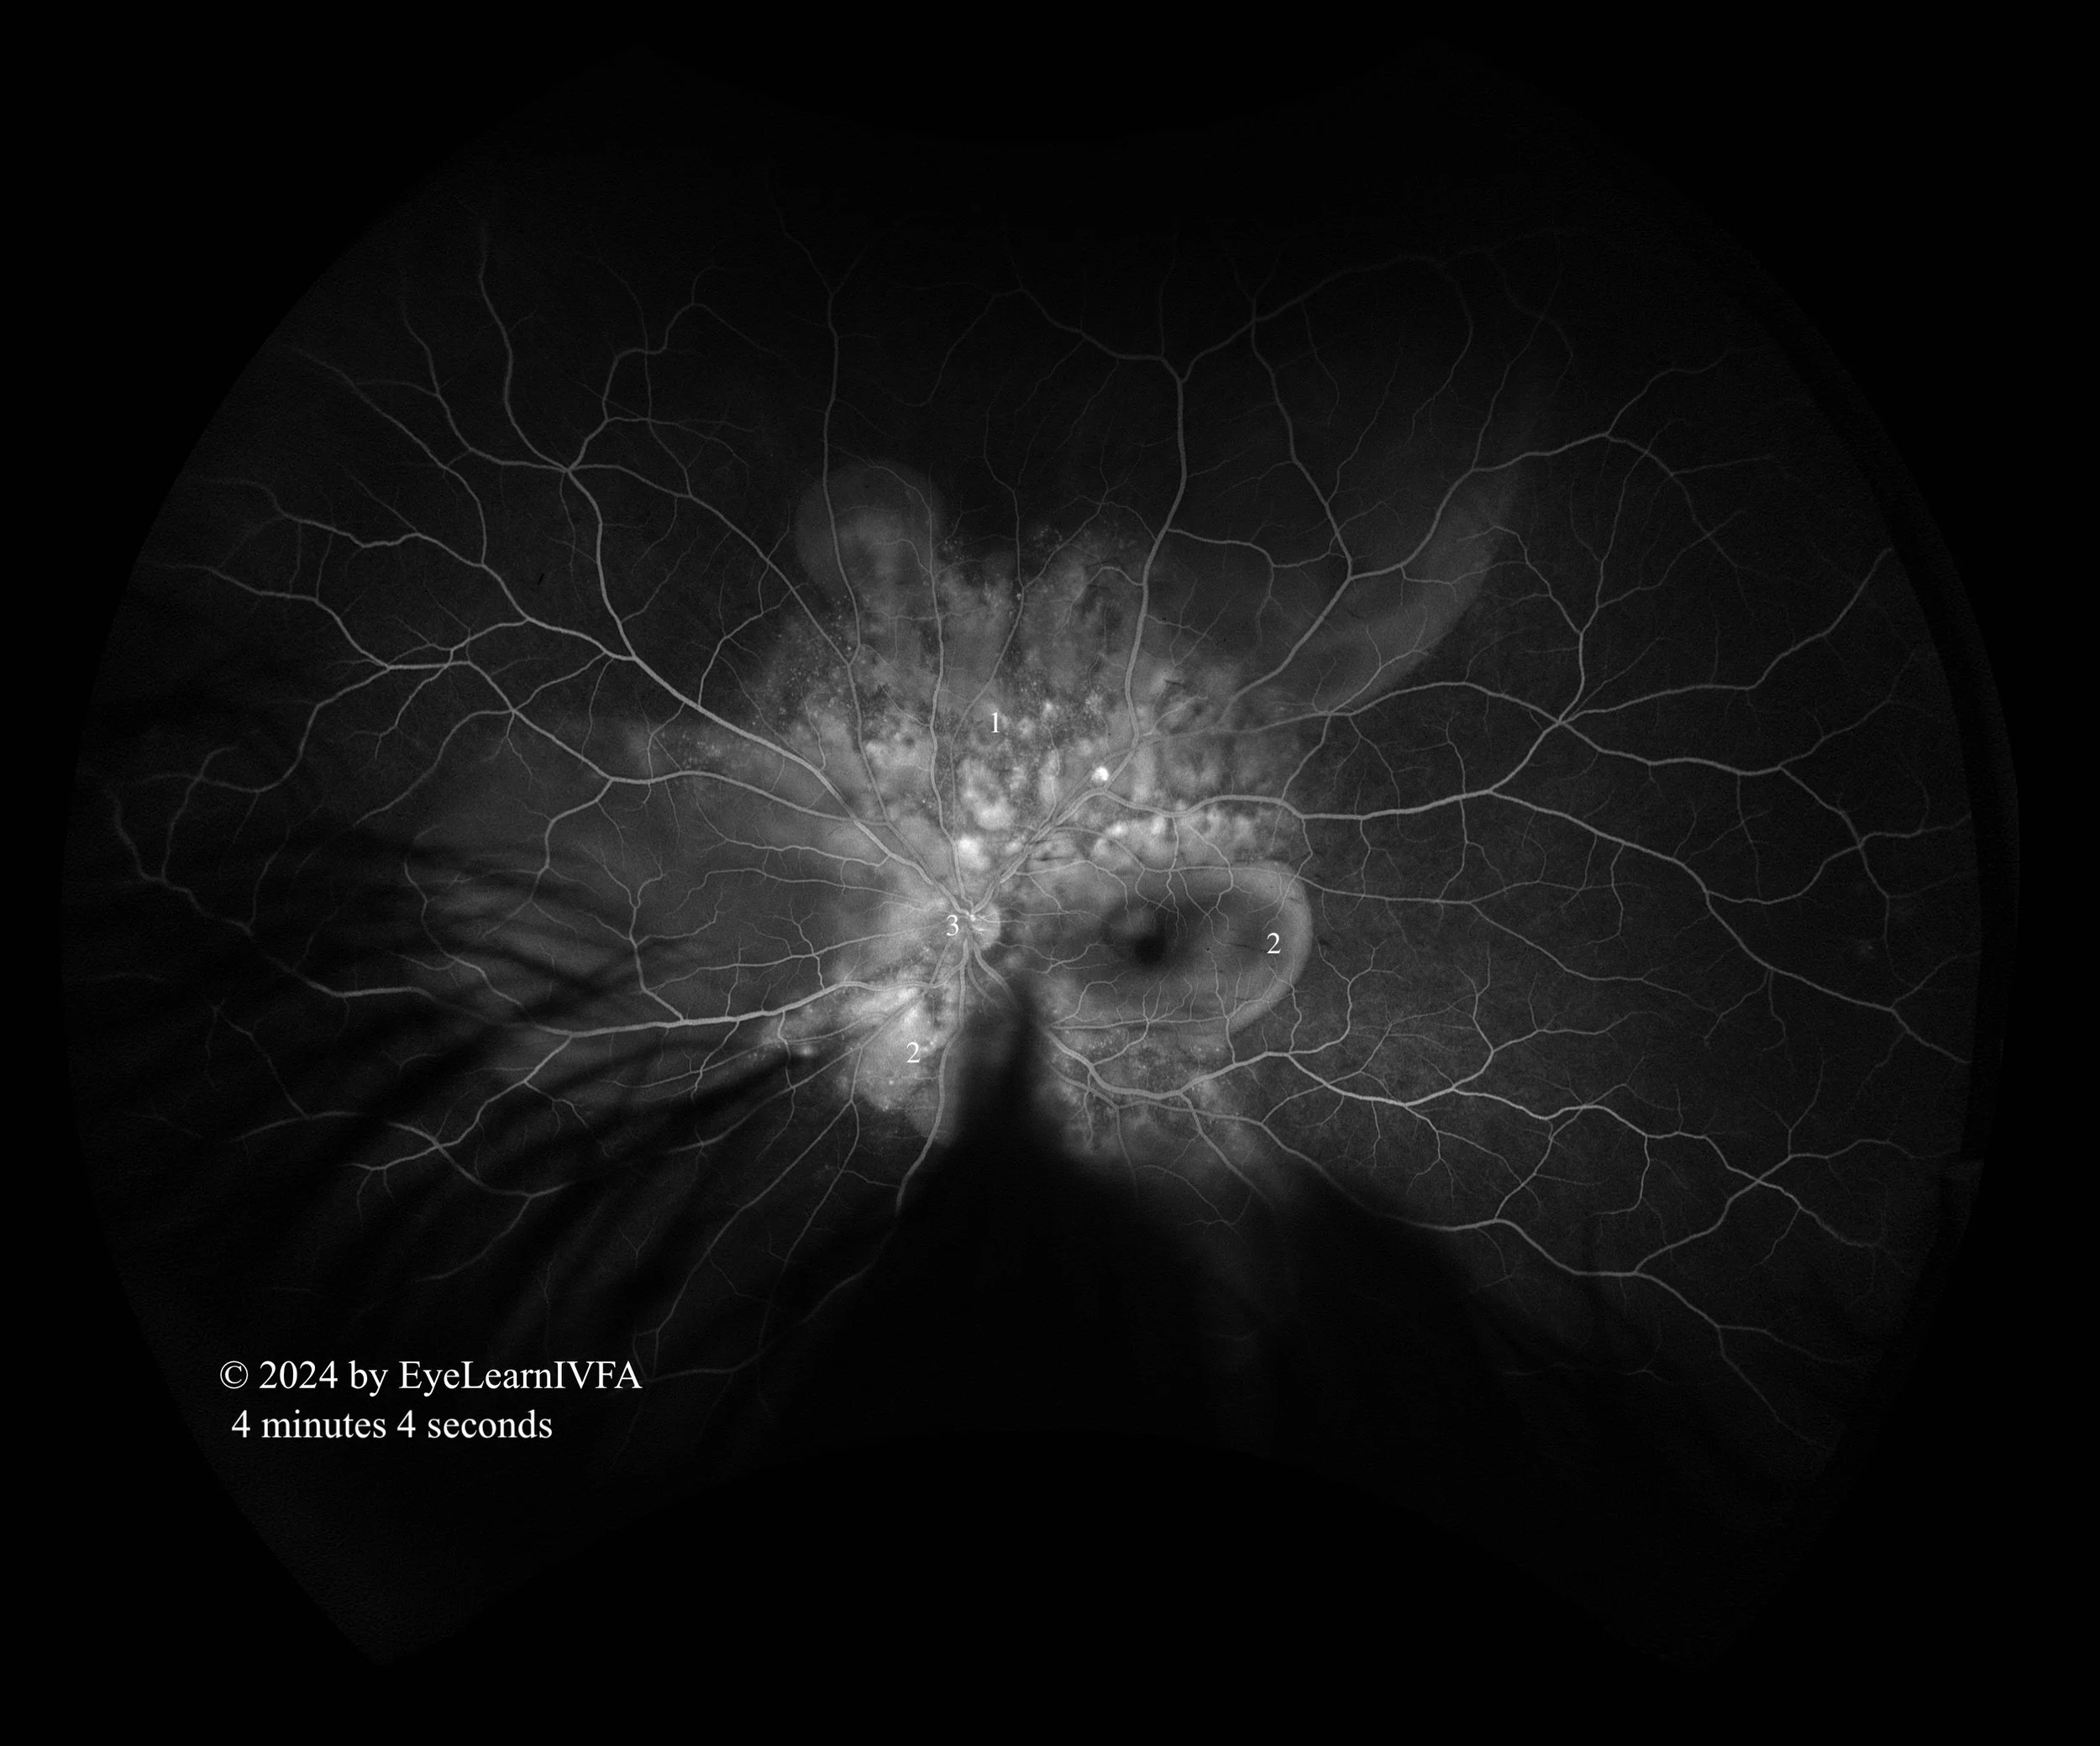

• IVFAs after 4 minutes in both eyes

Late Phase.

Key Features:

• Continued pattern of pinpoint areas of hyperfluoresence around nerve and macula - more obvious “starry sky” appearance (1)

• The left eye shows pooling of dye resulting in hyperfluorescence (2), with the central macula being hypofluorescent.

• Presence of hyperfluorescent optic nerve OS, with a ring of hypofluorescence (3).